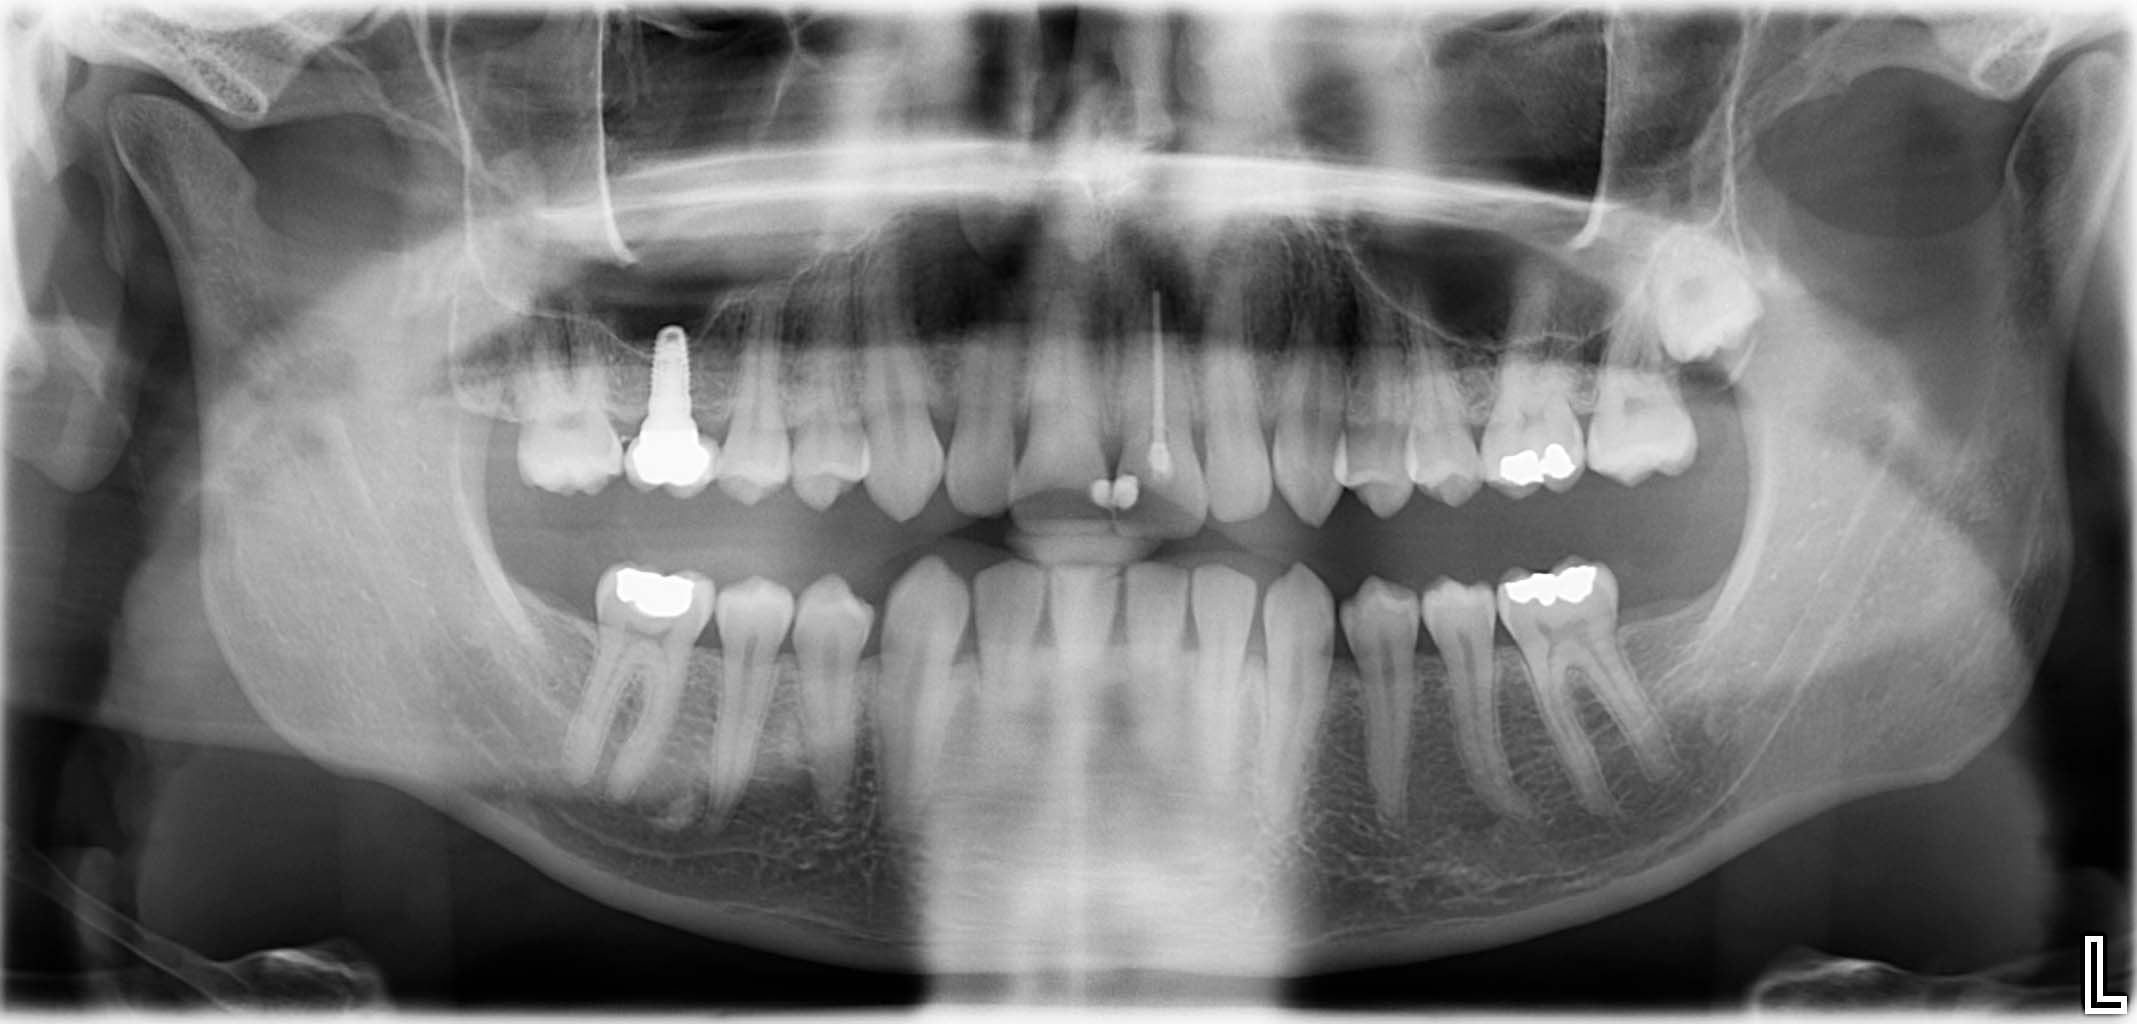

Ausgangssituation: Zahn 36 mit apikaler Beherdung, nicht erhaltungswürdig